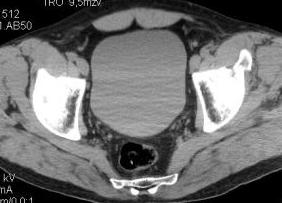

Уважаемые коллеги! Хотелось бы услышать ваше мнение. Мужчина 50л поступил с переломами костей таза. Закрытый перелом крыла подвздошной кости, переднего края вертлужной впадины справа.

Достаточно ли консервативного лечения, стоит ли беспокоиться о переднем крае? В приложении КТ.